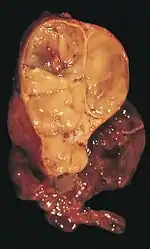

Les thymomes se présentent comme une masse bien définie du médiastin antérieur, proche du péricarde et dans un plan plus antérieur que les gros vaisseaux intrathoraciques (aorte ascendante et sa crosse, artère pulmonaire, veine cave supérieure). La masse peut être sphérique ou lobulée, mais présente un aspect homogène (plus rarement kystique) qui se réhausse après injection et peut contenir des calcifications[29].